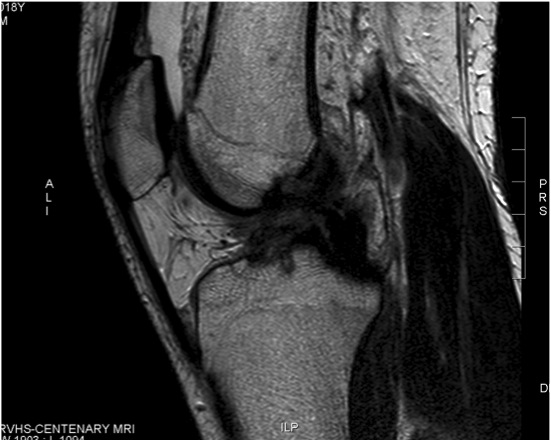

MRI

Chronic proximal avulsion LCL / Popliteus

Sagittal MRI showing torn ACL Coronal MRI demonstrating chronic avulsion LCL fibula head